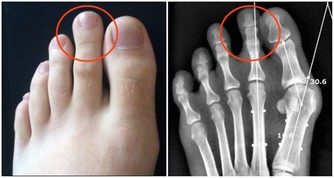

二、便血現象

很多人會莫名的出現便血,尤其是在大便時,便血更為嚴重。大家很有可能會把這種情況誤認為是痔瘡造成的,或者是當成上火。此外,除了便血之外,還有一些黏黏的液體,在排便時會帶出來。便血的出現跟腫瘤的生長位置有極大的關係,如果離肛門位置遠一些,便血出現的機率低,多數患者都有便血現象。